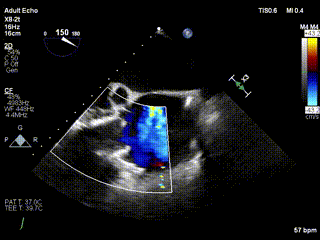

2021年12月24日,復(fù)旦大學(xué)附屬中山醫(yī)院葛均波院士團(tuán)隊(duì)成功應(yīng)用LuX-Valve Plus為一例極重度三尖瓣反流(TR)合并房顫、房缺的患者完成了經(jīng)血管三尖瓣置換術(shù),這是在前基礎(chǔ)上,本周完成的第三例經(jīng)血管三尖瓣置換手術(shù),葛均波院士、周達(dá)新教授等與心外科魏來教授、賴顥教授,心超室的潘翠珍教授、李偉教授及麻醉科的郭克芳教授共同完成了本周手術(shù),均獲得圓滿成功!患者術(shù)后超聲顯示無TR,臨床癥狀明顯改善。本周手術(shù)的成功也為LuX-Valve Plus救治性臨床研究添上了濃墨重彩的一筆。

三例患者入院后,葛均波院士團(tuán)隊(duì)周達(dá)新教授、潘文志教授、張?jiān)床┦俊㈥惿┦考靶某业呐舜湔浣淌?、李偉教?/strong>對(duì)患者的情況進(jìn)行詳細(xì)評(píng)估和討論,最終決定為三例患者選擇LuX-Valve Plus40mm、50mm和50mm型號(hào)的瓣膜進(jìn)行手術(shù)治療。手術(shù)后即刻拔除氣管插管,術(shù)后患者三尖瓣反流癥狀得到顯著改善,復(fù)查心超結(jié)果顯示人工三尖瓣瓣膜支架固定穩(wěn)定,瓣葉關(guān)閉形態(tài)未見異常,未見明顯反流。